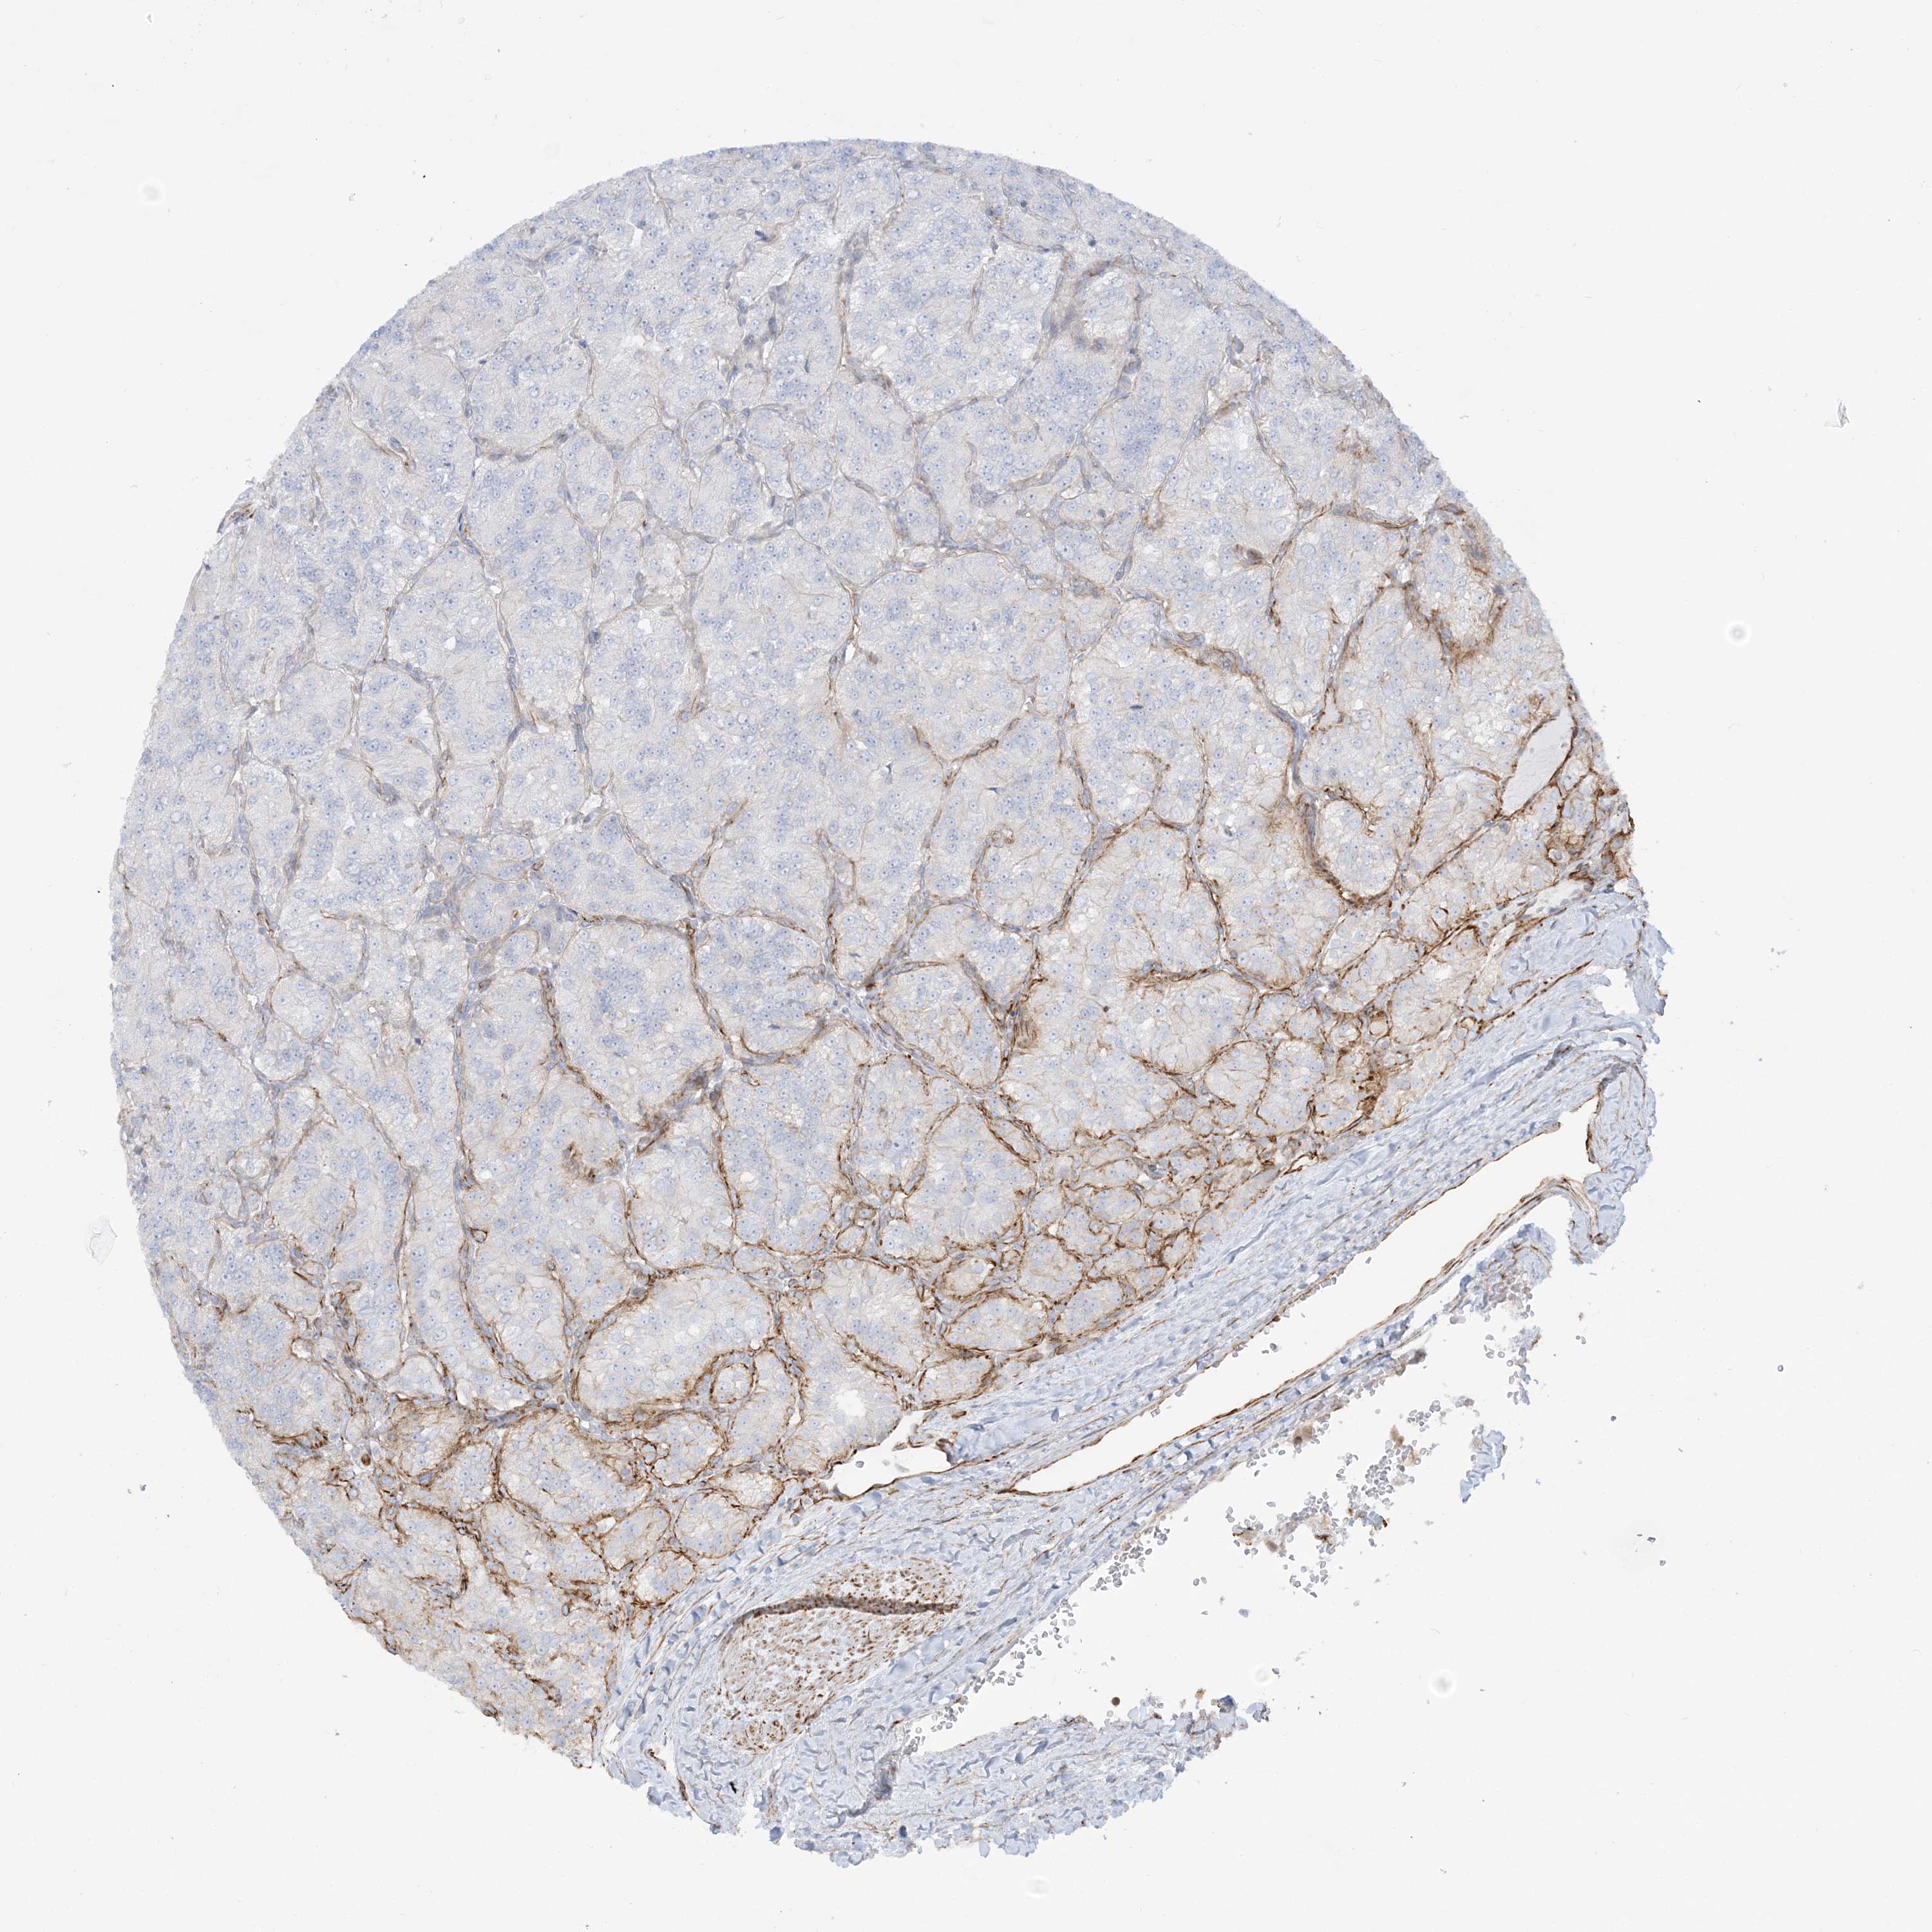

KIDNEY RENAL CLEAR CELL CARCINOMA (TCGA) - Interactive survival scatter ploti

The Survival Scatter plot shows the clinical status (i.e. dead or alive) for all individuals in the patient cohort, based on the same data that underlies the corresponding Kaplan-Meier plots. Patients that are alive at last time for follow-up are shown in blue and patients who have died during the study are shown in red.

The x-axis shows the expression levels (FPKM) of the investigated gene in the tumor tissue at the time of diagnosis. The y-axis shows the follow-up time after diagnosis (years). Both axes are complimented with kernel density curves demonstrating the data density over the axes. The top density plot shows the expression levels (FPKM) distribution among dead (red) and alive patients (blue). The right density plot shows the data density of the survived years of dead patients with high and low expression levels respectively, stratified using the cutoff indicated by the vertical dashed line through the Survival Scatter plot. This cutoff is automatically defined based on the FPKM cutoff that minimizes the p-score. The cutoff can be changed by dragging the vertical line or by entering a cutoff value in the square labeled "Current cut-off".

Under the Survival Scatter plot the p-score landscape (black curve; left axis) is shown together with dead median separation (red curve; right axis). Dead median separation is the difference in median mRNA expression between patients who have died with high and low expression, respectively. It is calculated as follows: median FPKM expression of dead patients with high expression - median FPKM expression of dead patients with low expression. This is intended to aid the user in visually exploring custom cutoffs and the associated p-scores and dead median separation.

Individual patient data is displayed and can be filtered by clicking on one or more of the category buttons on the top of the page. Categories describing expression level and patient information include: high, low, alive, dead, female, male and tumor stages. The scale of the x-axis can be toggled between linear and log-scale by clicking on the "x log" button. Mouse-over function shows TCGA ID, patient information and mRNA expression (FPKM) for each patient.

& Survival analysisi

Kaplan-Meier plots summarize results from analysis of correlation between mRNA expression level and patient survival. Patients were divided based on level of expression into one of the two groups "low" (under cut off) or "high" (over cut off). X-axis shows time for survival (years) and y-axis shows the probability of survival, where 1.0 corresponds to 100 percent.

SCLT1 is not prognostic in Kidney Renal Clear Cell Carcinoma (TCGA)

TCGA RNA samplesi

RNA-seq data is reported as average FPKM (number Fragments Per Kilobase of exon per Million reads), generated by the The Cancer Genome Atlas (TCGA) .

Normal distribution across the dataset is visualized with box plots, shown as median and 25th and 75th percentiles. Points are displayed as outliers if they are above or below 1.5 times the interquartile range. FPKM values of the individual samples are presented next to the box plot.

Average pTPM 3.8